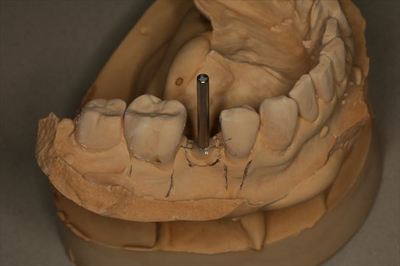

KaVoの咬合器に上下歯列模型をマウントしました。

CTデータと重ね合わせてシミュレーションします。

ドリルガイドであるサージカルステントを作成します。